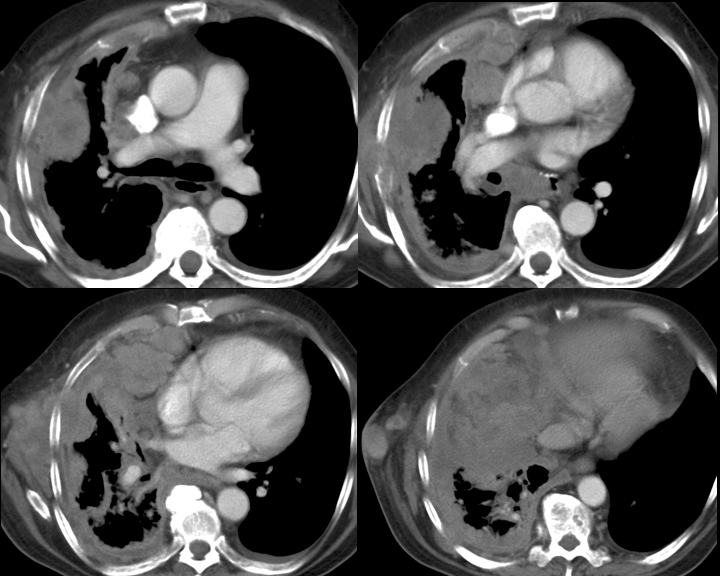

Gallery Pleural mesothelioma CT

mesothelioma CT